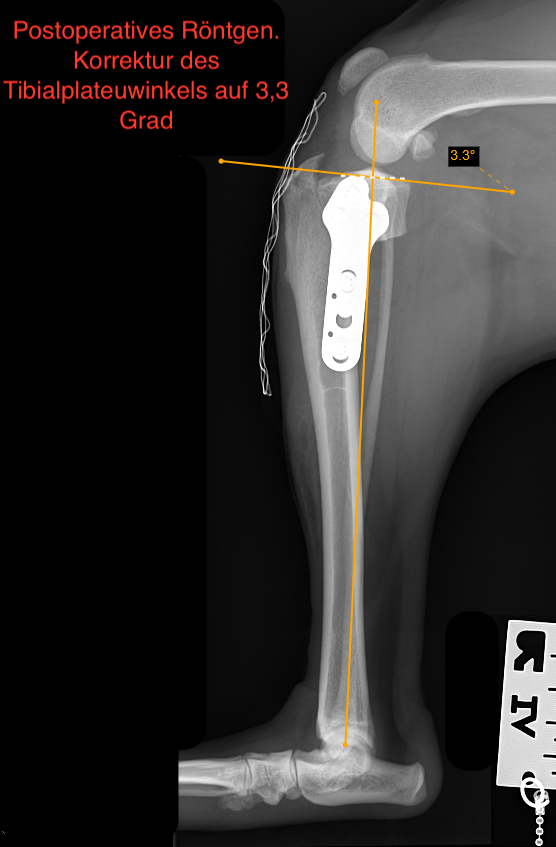

Die TPLO (Tibial Plateau Leveling Osteotomy) ist ein bewährtes Verfahren zur funktionellen Stabilisierung des Kniegelenks und ermöglicht eine zuverlässige und langfristige Verbesserung der Gelenkfunktion.

Arthrex TPLO Platte

Wir verwenden Implantate der renommierten Firma Arthrex, die auch Implantate für die Humanmedizin herstellt. Hochpräzise Implantate, individuell angepasst an die Größe und Anatomie jedes Tieres.